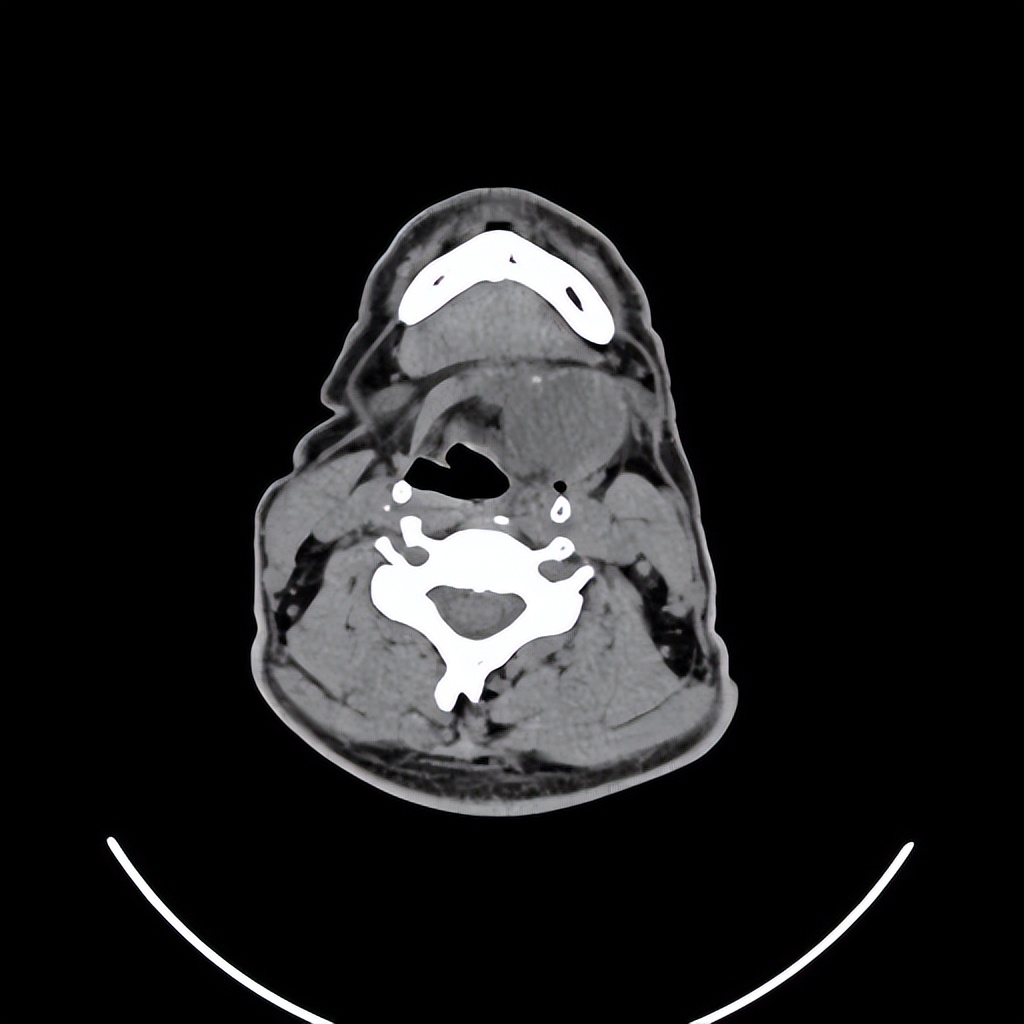

来自广东梅州的管叔,最近发现颈部肿物2周,不痒,不痛,自觉问题不大。但是肿物越来越大了,在家人的劝说下来到佛山复星禅诚医院耳鼻喉做了检查发现是颈部的先天性囊肿。

这个年龄阶段发现颈部的先天性囊肿是比较少见的,一般这种病没有多少的不舒服,但需要做手术切除才可以根治。一般手术早点做效果要好一些,如果囊肿长的比较大了,手术的范围也会相应的扩大,术后恢复就可能会慢一些,手术的风险也会相应的增大。

颈部肿物目前做小切口内镜微创手术比较适合,这样既能切除干净肿物,也会兼顾美观。关于颈部肿物如果您有任何的问题,欢迎留言和耳鼻喉郑立岗医生进一步交流。